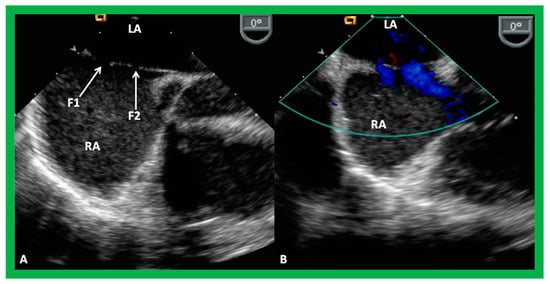

9. Follow-Up after Device Occlusion